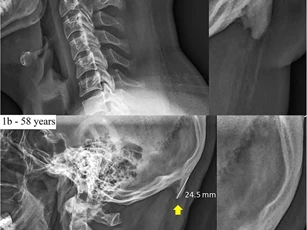

Sự thật việc cúi đầu sử dụng những chiếc điện thoại thông minh dường như đang thay đổi cấu trúc hộp sọ của chúng ta, khiến những chiếc xương gai bí ẩn xuất hiện.